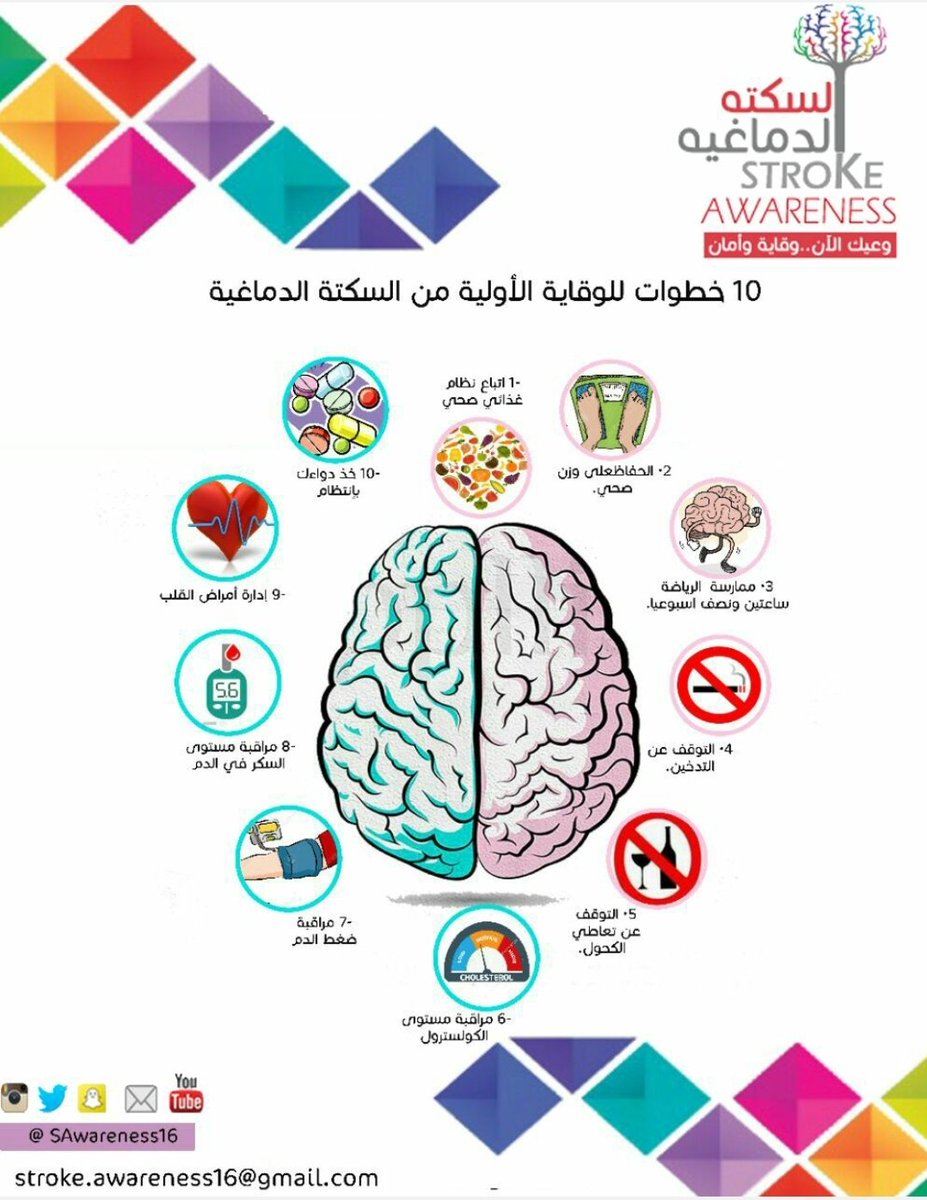

💥عوامل الخطورة

🧠ارتفاع الضغط

🧠السكري

🧠الكوليسترول

🧠التدخين

🧠قلة النشاط البدني

🧠أمراض القلب

🧠العلاج الوقائي

خطوة هامه لمنع إعادة الاصابه مستقبلا

(معرفة السبب الأساسي والسيطرة عليه)

♦️متابعة

(سكر/ضغط/كوليسترول/تدخين/رياضه)